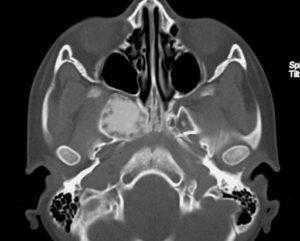

(Слева) На корональной КТ в костном окне определяется ПФД с поражением глазницы, петушиного гребня, решетчатого лабиринта, средней носовой раковины справа. Оцените типичную картину «матового стекла». Носовая перегородка смещена влево.

(Справа) На аксиальной МРТ (Т2ВИ) у этого же пациента определяется выраженный гипоинтенсивный сигнал в пораженных костях. Поражение однородное и сопоставимо с «матовым стеклом» на КТ. При большем количестве фиброзной ткани ожидаемы очаги с более интенсивным сигналом и более длительным временем повторения.